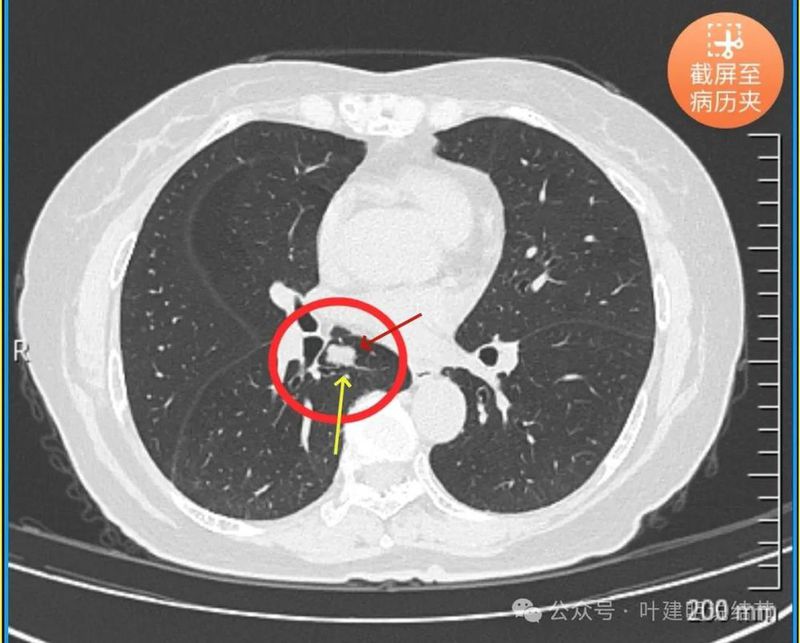

右肺下叶这个病灶从连续的层面看,连续较为光滑、有一定膨胀性,部分表面有浅分叶,病灶内部无明显钙化,随访无显著变化(当然时间还短),没有明显侵犯邻近血管或支气管,但紧贴、关系密切。我之前碰到好几例类似的实性小结节随访没有明显进展的,最后证实是低分化腺癌的,我还有专门在公众号总结过这类病例的影像特点。我个人觉得仍然恶性不能够除外。如果不是恶性,那么错构瘤或者良性肿瘤的话,手术的时候肺的表面切开一剥就出来了。通过比较小的一个手术就能把病灶拿掉,而且明确了诊断。如果确实是实质性的非良性的肿瘤,那么他如果往旁边生产侵犯很容易就影响到血管。个人感觉利弊综合考虑还是手术探查更加稳妥。意见供参考!

感悟:

这个病例在结友女儿问诊我之后,我是建议她开刀为妥,因为考虑恶性的可能性不能排除,而且真恶性则风险较大,真若错构瘤则手术并不需要切除肺叶。但后面家属带她到某省级医院看了大专家,教授告诉她良性的,不需要开刀,老人很高兴。她女儿说,也就没有办法再告诉她妈妈这个病灶也不能除外恶性,或仍有医生是建议开刀的。但愿吧!希望真不是恶性,那最理想。我倒是真的不放心的,下面这几例都是恶性的,你说能安心吗?

右上实性病灶是神经内分泌癌,考虑典型类癌。